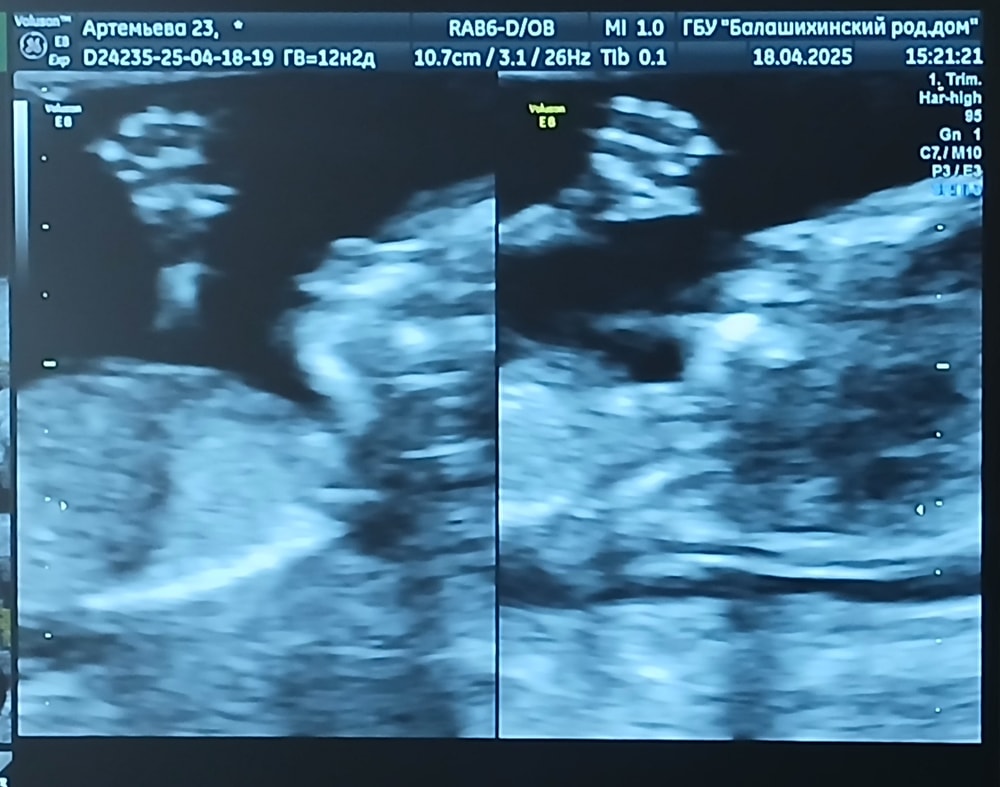

Повторный 1-й скрининг (бесплатный от ЖК)🥰

Анализы, скринингиВсем привет!) Сходила еще раз сегодня на скрининг🥰 мне всё понравилось,было даже лучше видно,чем на платной основе,врач всё в конце объяснила, дала заснять на видео самые удачные моменты😍😍 фоточки две дала самые прекрасные в распечатанном виде, и их же я сфоткала,прикреплю🥹 предположила,что будет мальчик

Я счастлива❤️ Итоговый срок 13 недель + 3 дня

Машем всем привет🥹🫶🖐